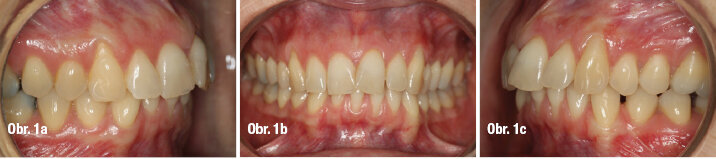

Pacientka navštívila naši praxi kvůli kloubním problémům – stěžovala si na obtíže v pravém TMK. Při intraorálním vyšetření jsme diagnostikovali II. třídu dle Anglea na levé straně, která se zhoršovala během dorazové fáze, mírnou mandibulární asymetrii s posunem dolní středové čáry zatímco horní střední čára korespondovala s filtrem, absenci 36, gingivální recesy nahoře i dole, stěsnání a klikání v kloubu (obrázky 1a–c).

Na telerentgenu pacientky byla diagnostikována II. skeletální třída, protruze horních řezáků a inklinace dolních lingválně. Na ortopantomogramu byla zjevná ztráta 36, úroveň kosti a celkový biologický faktor chrupu byly vyhovující (obr. 3a–b).